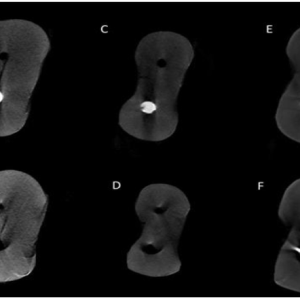

اثربخشی سیستمهای روتاری D-RaCe، SP1 و R-endo در حذف مواد استفاده شده برای پر کردن کانال ریشه از دندانهای آسیای بزرگ فک پایین انسان: یک مطالعه با استفاده از میکرو سیتی

نویسندگان: پریناز بیکیان قویدل، امیر عباس مشاری و سهراب طور سوادکوهی چکیده:مطالعه حاضر بازدهی درمان مجدد با فایلهای روتاری D-RaCe، SP1 و R-Endo در حذف